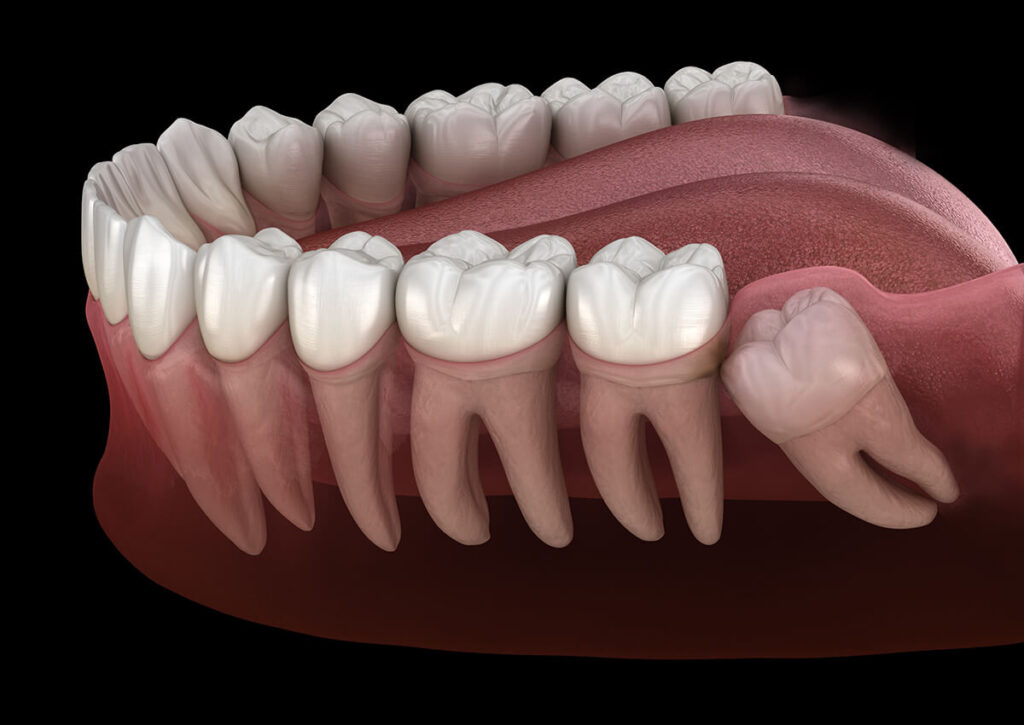

What is Wisdom Teeth Removal?

Wisdom teeth removal is a dental procedure performed to extract the third molars — the last set of teeth that usually appear between ages 17 and 25. In many cases, these teeth do not have enough space to grow properly, which can cause pain, infection, swelling, or misalignment.

Removing them early helps prevent:

- Tooth crowding or shifting

- Jaw pain or stiffness

- Infection or gum inflammation

- Tooth decay in nearby teeth